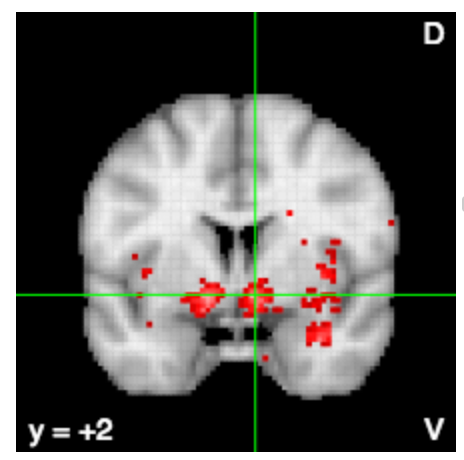

Friston et al. (1994) Human Brain Mapping

food, weight, obese, eating, foods, obesity, reward, energy, hunger, calorie, intake, bmi, mass, body, satiety, normal, cues, responsivity, women, overweight, appetite, individuals, caloric, increases, lean, index, fat, pictures, gain, hungry, images, bed, palatable, craving, receipt, water, overeating, meal, kg, motivation

neurosynth.org